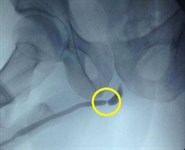

После установки температурных датчиков, под контролем УЗИ чрескожно, через специальные крио-зонды в опухоль вводят аргон или азот, который быстро замораживает ее до -40ОС. В течение 5-15 минут происходит полное прекращение кровообращения на пораженном участке. Затем в опухоль подается гелий, чтобы разогреть ткани до нормальной температуры. Резкое повышение температуры вызывает разрыв клеточных мембран и некроз тканей опухоли, в результате которого она погибает.